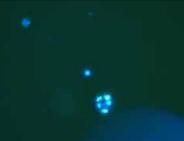

使用第 0 天

使用第 42 天

採用熒光染色法觀察馬拉色菌定植情況

馬拉色菌顯著減少!